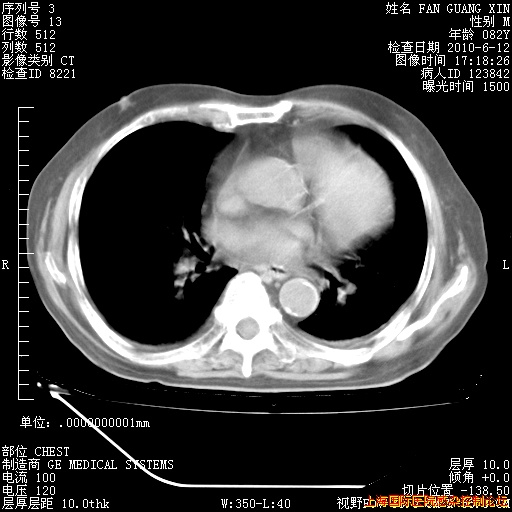

今天复查CT

今天CT

整整相隔30天的肺部CT好像有所好转啊。甲强龙减量第3天,需要观察体温。

海管,自昨日你和我通完话后,不知您岳父消化道症状有无缓解?体温怎样?阅读7.12日胸部ct,个人认为目前激素治疗是有效的,甲强龙减量是适宜的。因在抗痨治疗,需密切观察肝功、肾功能和血常规。不过,老年、长期住院和大量使用激素,很担心菌群失调发生